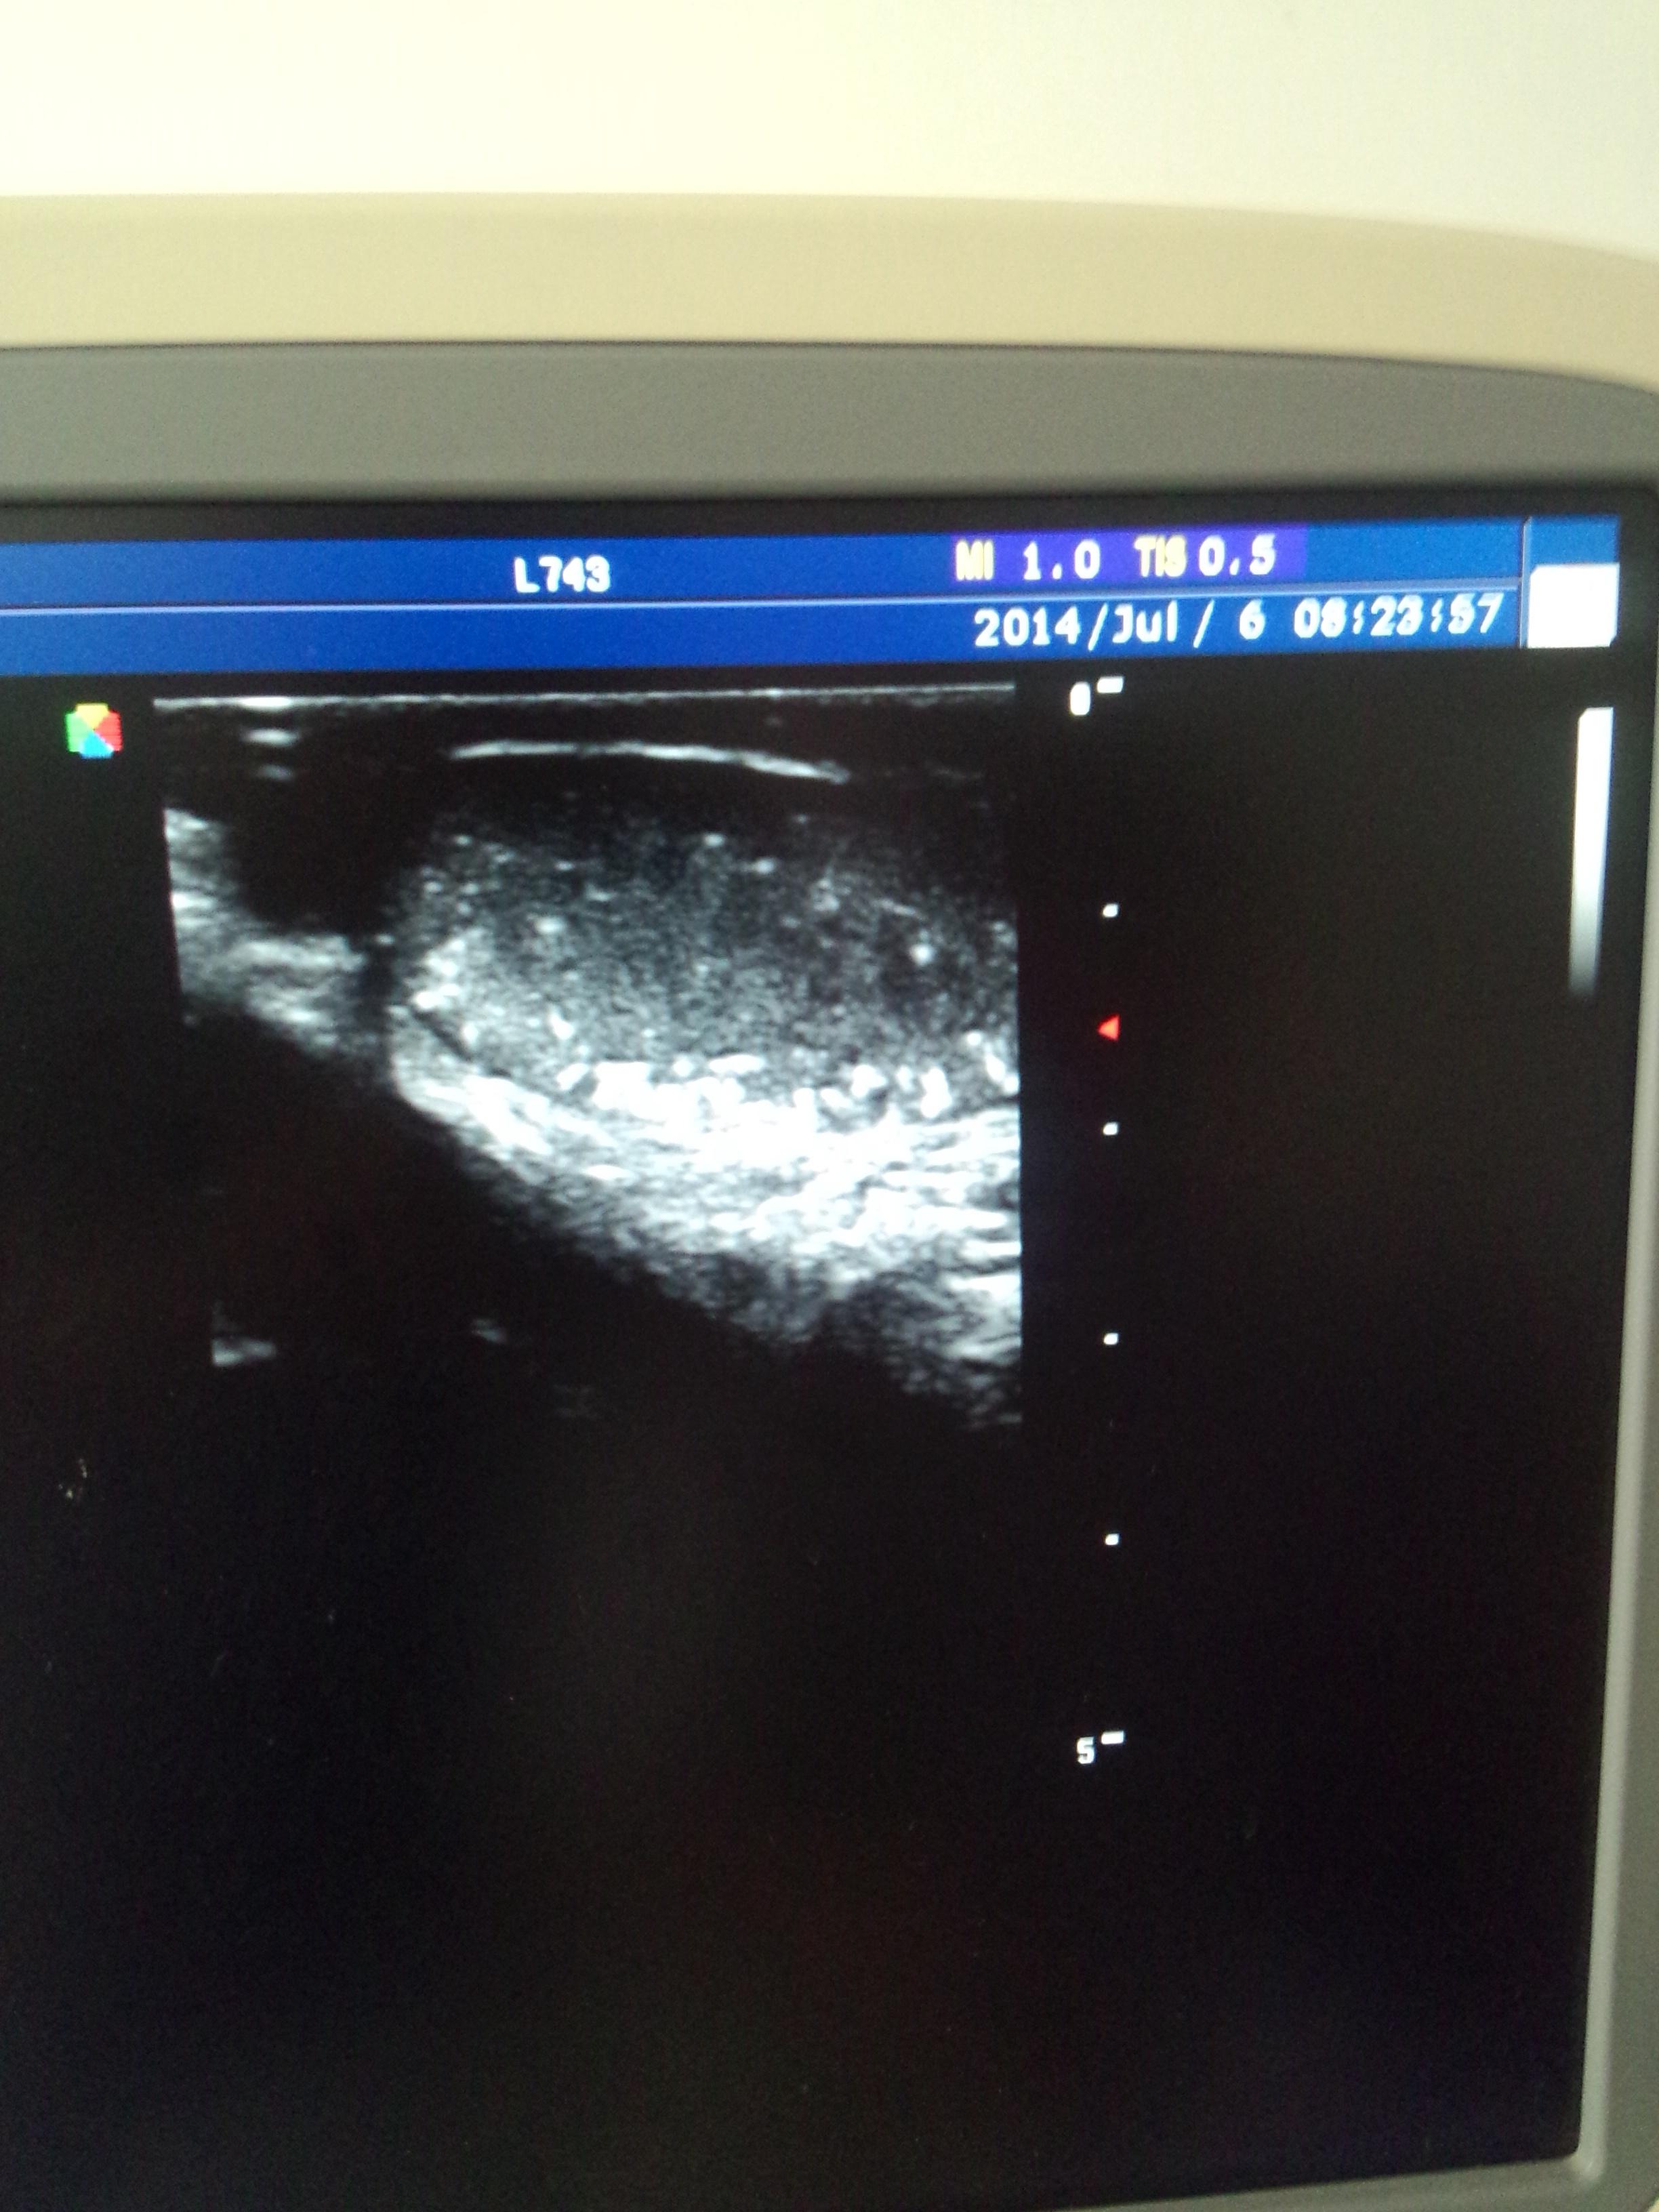

患男14岁,双侧睾丸弥漫性钙化。

患男14岁,双侧睾丸弥漫性钙化,右侧副睾头囊肿,这是个什么意思?

睾丸微结石